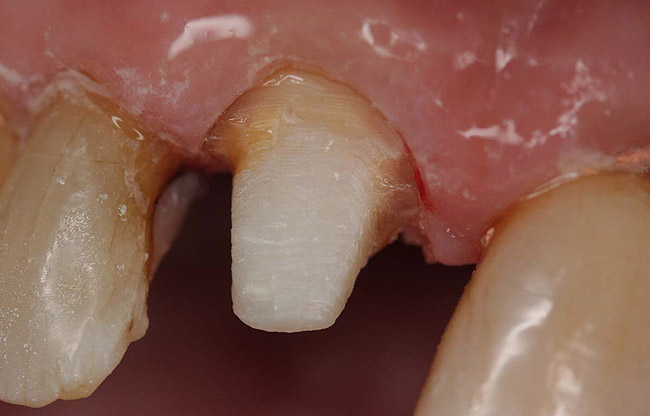

Case 1

A Class IN maxillary bicuspid was previously restored with a fiber post and an all-porcelain crown (Figure 1). The forces of the oral environment resulted in fracture of the fiber post and crown failure. The remaining fiber post in the root was removed, and anti-rotational areas were prepared for a cast post (Figure 2). A gold cast post was constructed at a dental laboratory, using an indirect technique (Figure 3). A porcelain-fused-to-metal (PFM) crown was constructed with a bevel finish to provide a ferrule and reduce forces on the post (Figure 4 and Figure 5).

Figure 3  Cast post to restore the second bicuspid.

Figure 3